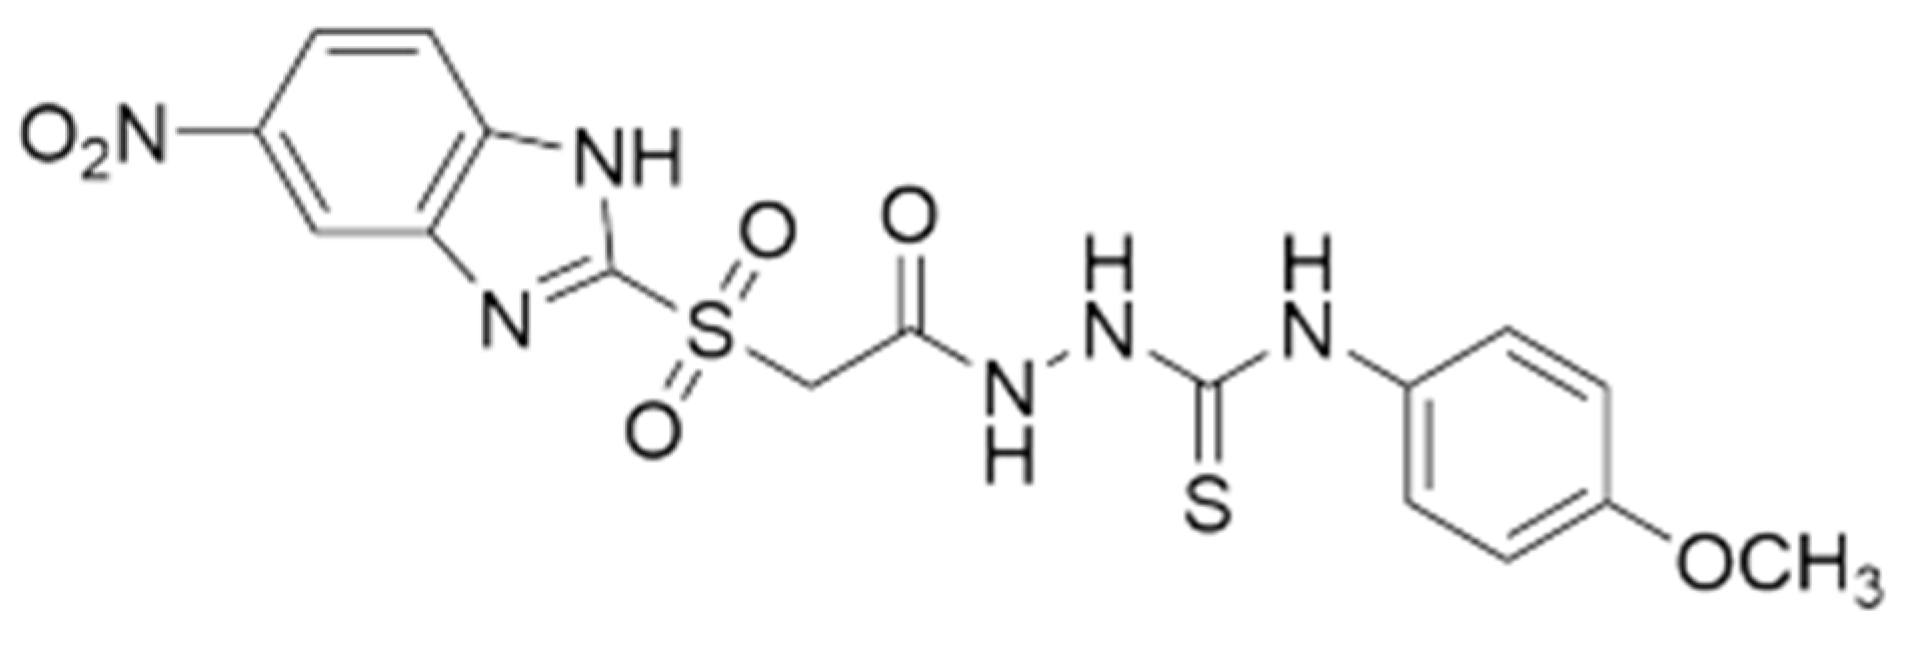

- Popovici, C.; Pavel, C.-M.; Sunel, V.; Cheptea, C.; Dimitriu, D.G.; Dorohoi, D.O.; David, D.; Closca, V.; Popa, M. Optimized Synthesis of New Thiosemicarbazide Derivatives with Tuberculostatic Activity. Int. J. Mol. Sci. 2021, 22, 12139. [Google Scholar] [CrossRef]